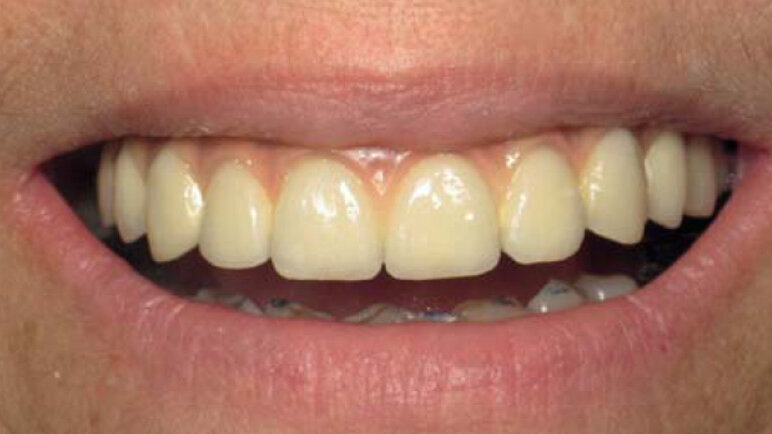

Sourire de notre patiente.

La céramique est maquillée pour s’approcher de l’aspect de dents naturelles. Une fausse gencive rose permet de palier au manque tissulaire préalable (Figs. 14, 15 et 16).Notre patiente a retrouvé ses dents et ne sera restée sans denture fixe que quelques heures. Les suites opératoires auront été minimes et la durée totale du traitement été de 4 mois.